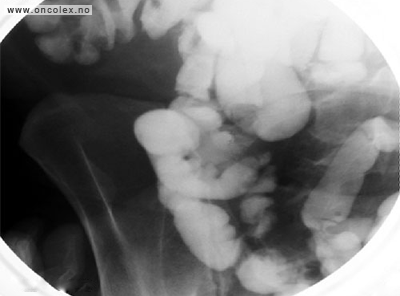

CT  med kontrast er den mest brukte røntgenundersøkelsen. Kontrastvæsken gis gjennom en kanyle (venflon) i armen. Svulster i leveren synes oftest best på MR. MR eller CT-tynntarm kan påvise nevroendokrine svulster i tynntarmen som ikke ses på vanlig MR/CT.

Bildeeksempler